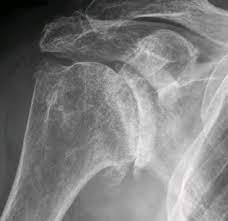

1. X-ray 검사 :

정형외과에 방문하시게되면 가장 많이 하시게 되시는 검사입니다. 가장 기본적이면서도 가장 먼저 감별해야할 위험한 진단을, 예를 들면 골절이나 골종양 등을 발견할 수 있게 해주는 값싸고도 고마운 검사입니다.

동결건에서 X-ray는 사실 진단에 큰 역할을 하기보다는, 그 기저 질환이 무엇인지 알아낼 수 있는 장치로써, 기본적으로 촬영하게 되는 검사입니다.

앞에서 말씀드린 이차성 동결건의 원인 중 하나인 석회성 건염이 있는지를 감별하게 해주며, 관절염이 심하게 진행되신 분들도, 단순 엑스레이 검사를 통해서 감별이 가능합니다.

그러니 병원 방문 전 어느정도 동결건에 대해서 인터넷으로 검색해보고 가셨다고 하시더라도, "X-ray로 별거 안보이는데 왜 찍나요? 돈벌려고 하는거 아닌가요?"라는 말씀은 하지 말아주세요 ^^;;